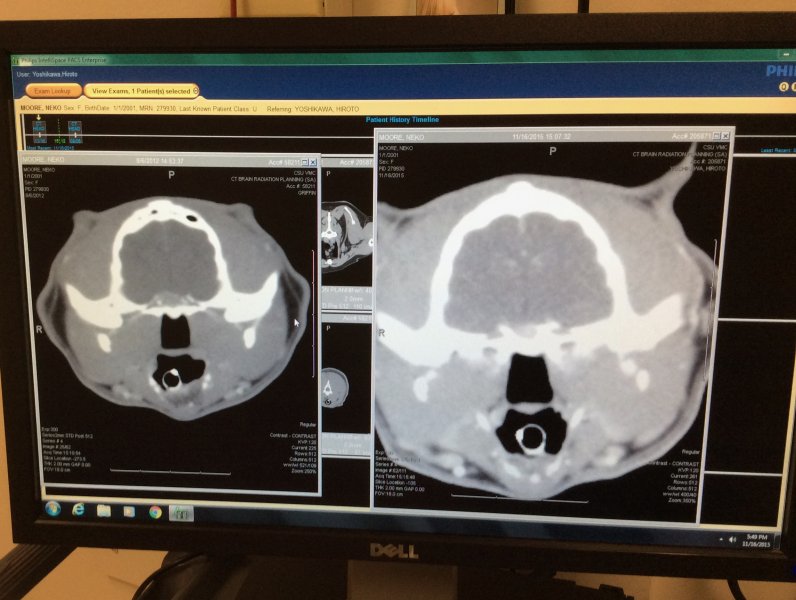

Talking with radiation oncologist re: the CT scan @ 9:00 am.